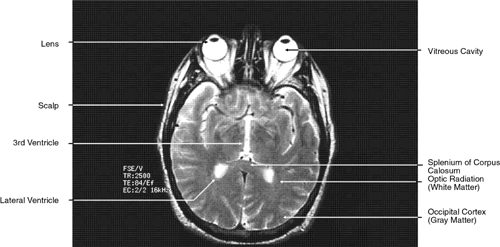

The globe is shown in Figure 12. The orbit and periorbital structures are shown in Figures 13 through 16, and the optic canal is shown in Figures 17 through 26. The cavernous sinus and optic chiasm are shown in Figures 27 and 28, and the posterior visual pathway and cranial nerves are shown in Figures 29 through 33.

T2-weighted images can be produced at the same time as proton density images. In this case both the TR and TE are prolonged. By allowing all tissues to relax maximally, the most intense signal will be produced by the tissue with the longest T2 (that is, the tissue that remains coherent the longest). A particular tissue's T2, which typically ranges between 25 and 150 msec, is usually much shorter than its T1. To obtain a T2-weighted image, both the TR (>2,000 msec) and the TE (50 to 150 msec) are long (Fig. 9). In such cases, vitreous and cerebrospinal fluid give the most intense images and fat, white and gray matter, bone, and air give the least intense images.